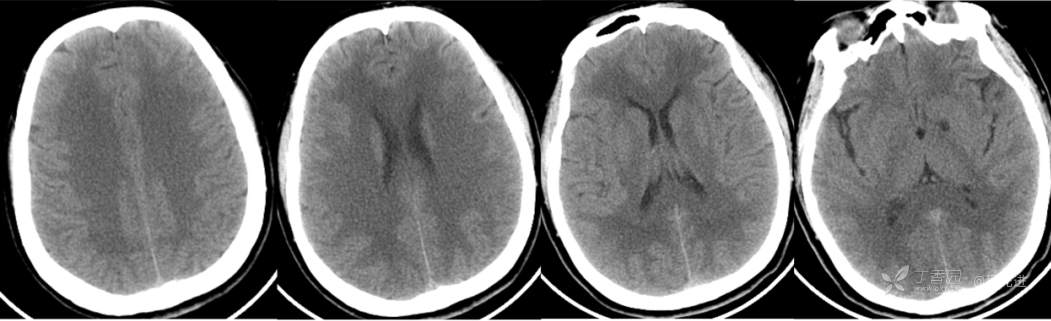

CT平扫